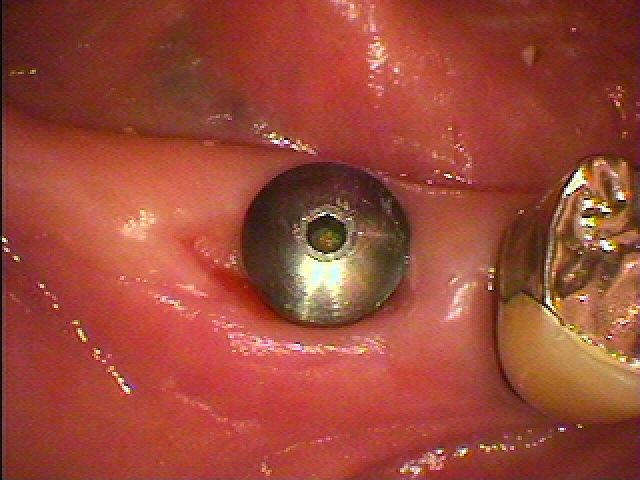

状態がよい時に抜歯即時インプラント埋入をさせていただきます

しっかりとしたインプラントが埋入できました